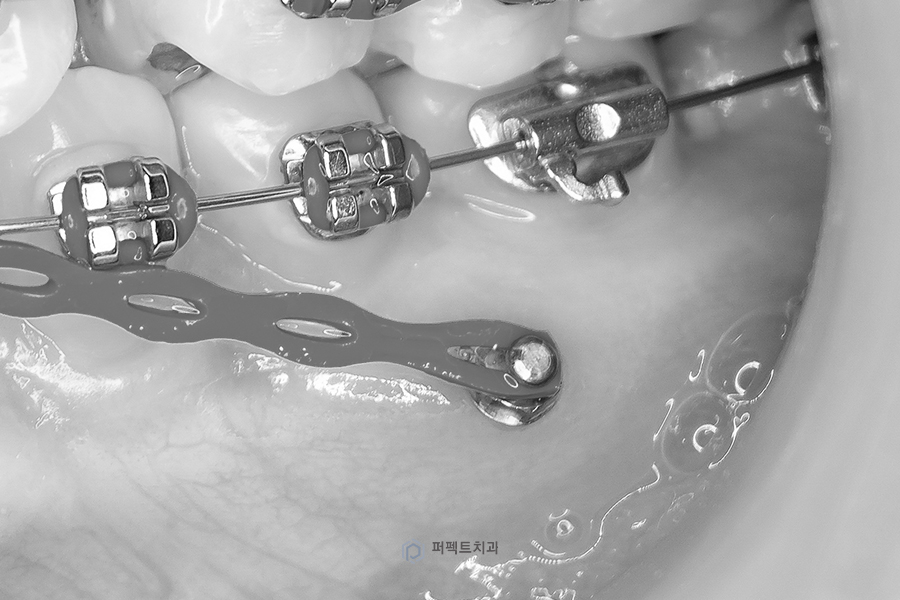

치아교정 시 미니스크류를 사용하지 않고 장치와 철사만으로 치아 이동을 하는 경우 원하는 치아이동을 얻을 수 있지만, 그에 대한 반작용으로 원치 않는 치아 이동이 생길 수도 있습니다. 하지만 미니스크류를 사용하게 되면 원치 않는 치아 이동은 막아주고 원하는 치아 이동만 달성하여 교정 치료 기간을 단축 하는 데에도 도움이 됩니다.

돌출감 때문에 교정을 하는 경우에도 미니스크류가 사용될 수 있습니다. 돌출을 해소하기 위해서는 보통 작은 어금니를 발치하고 앞니를 발치 공간 방향으로 밀어 넣어서 돌출감을 개선하게 됩니다.

이 때 미니스크류를 식립하지 않고 어금니에 지지해서 앞니를 당기는 경우에는 앞니도 들어가겠지만 그에 대한 반작용으로 어금니도 앞으로 오면서 발치 공간이 닫히게 됩니다.

즉, 앞니가 들어가는 양이 한계가 있기 때문에 돌출이 심하신 분들은 많은 양의 돌출감을 개선할 수 없게 됩니다. 이런 경우 어금니 부위에 미니스크류를 식립하고 미니스크류에 지지해서 앞니를 당겨주면 어금니가 앞 쪽으로 오는 걸 막아주면서 앞니를 최대한 뒤로 이동시킬 수 있기 때문에 더 큰 돌출감 개선이 가능해집니다.